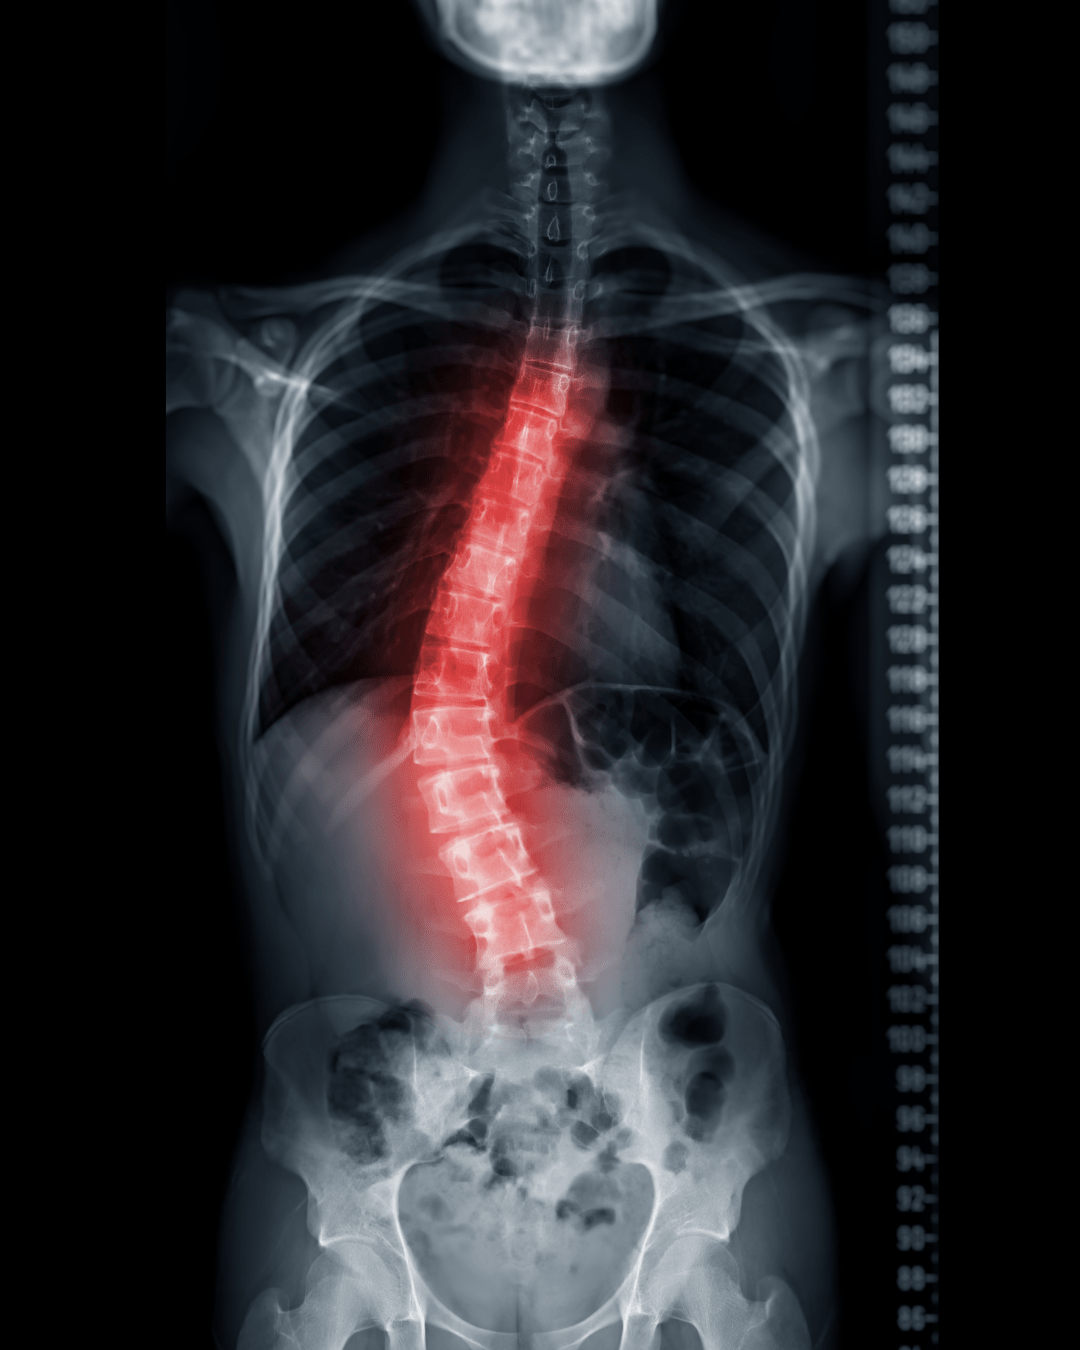

Escolioses

A escoliose é uma deformidade tridimensional da coluna vertebral, mas que no plano frontal é apercebida como uma curvatura lateral (em forma de S ou C). É uma patologia frequentemente diagnosticada em adolescentes. Apesar de a escoliose pode ocorrer em pessoas com condições como paralisia cerebral e distrofia muscular, a causa da maioria da escoliose infantil é desconhecida (idiopática).

A maioria dos casos de escoliose são ligeiros, mas algumas curvas pioram à medida que as crianças crescem. Uma escoliose grave pode ser incapacitante. Uma curvatura da coluna especialmente severa pode reduzir a quantidade de espaço dentro do peito, dificultando o bom funcionamento dos pulmões.

As crianças que têm escoliose ligeira são acompanhadas de perto, geralmente com raios X de toda a coluna vertebral (RX extra-longo), para ver se a curva está a piorar. Em muitos casos, não é necessário qualquer tratamento. Algumas crianças terão de usar um colete para impedir que a curva piore. Outras podem precisar de cirurgia para corrigir curvas severas.